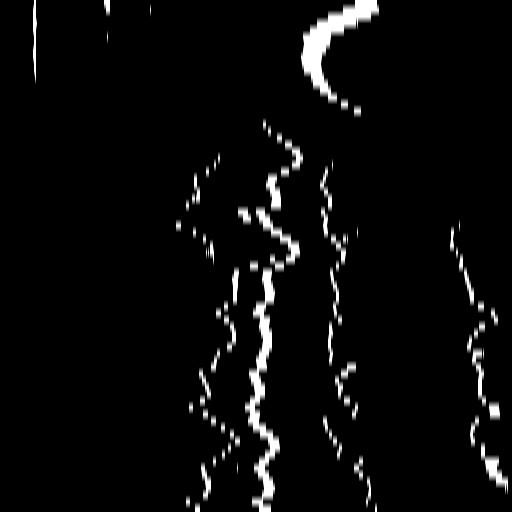

A.2 Temporal Coherency

Our method takes an entire X-ray video as input, thus producing segmentation results with better temporal coherency. Temporal coherency is essential for making medical diagnoses, especially when dealing with blood flow in vessels. Therefore, we conduct visual comparisons between our method and other compared methods by slicing horizontally or vertically and stacking the segmentation results. The results in Figure 12 show our method strikes a better balance between segmentation accuracy and temporal coherency. While other baseline methods either produce false segmentation results or do not maintain consistent prediction along the temporal dimension.